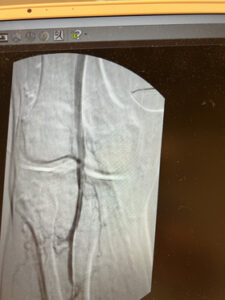

Ενδαγγειακή αποκατάσταση απόφραξης της ιγνυακής αρτηρίας

24 ωρη παραμονή στην κλινική

Ενδαγγειακή επαναγγείωση της ιγνυακής αρτηρίας

πλήρη ύφεση της συμπτωματολογίας

μετά απο 24 ώρες επιστροφή στην καθημερινότητα